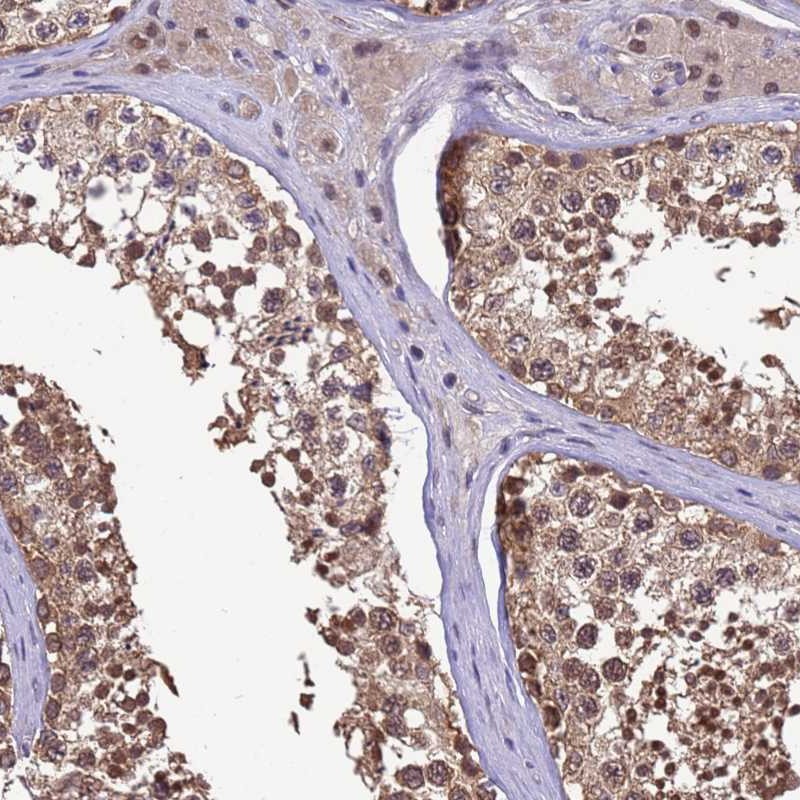

Immunohistochemical staining of human testis shows moderate cytoplasmic and nuclear positivity in cells in seminiferus ducts.